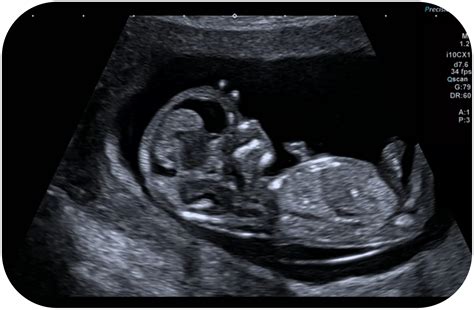

Considerată cea mai importantă ecografie a sarcinii, aceasta oferă detalii extinse despre anatomia și fiziologia copilului. Medicul examinează sistematic structuri precum calota craniană și creierul, fața (pentru despicături), inima (camerele și vasele mari), stomacul, rinichii, vezica urinară, coloana vertebrală și membrele. Se evaluează, de asemenea, placenta (localizarea, ex. placenta previa dacă este prea joasă) și lungimea colului uterin, pentru a preveni riscul de naștere prematură. Această ecografie screening pentru anomalii este recomandată tuturor gravidelor, deoarece identifică majoritatea malformațiilor majore (ex. defecte de tub neural precum spina bifida, anomalii cardiace, defecte renale). Depistarea timpurie permite planificarea nașterii într-un centru medical adecvat, uneori cu posibilitatea intervențiilor chirurgicale postnatale sau chiar intrauterine.

Ecografiile de morfologie fetală sunt investigații detaliate, esențiale pentru evaluarea dezvoltării anatomice și fiziologice a fătului.